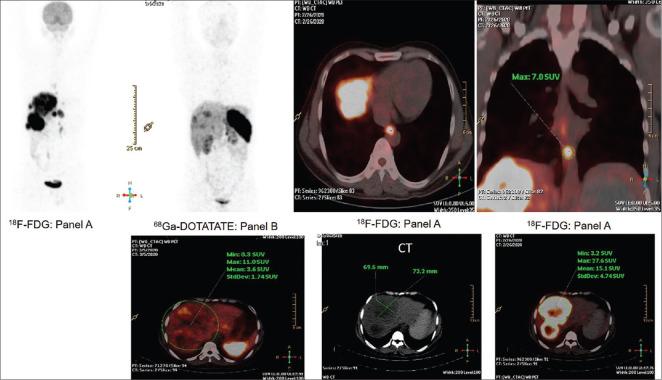

The correlates of dual tracer positron emission tomography and computed tomography (PET-CT) (F-fluorodeoxyglucose [F-FDG] and Ga-DOTATATE) in patients of Grade 3 neuroendocrine neoplasms (NENs) are presented. The first, a patient of gall bladder NEN, operated, with histopathology suggestive of high-grade well-differentiated neuroendocrine tumors with MiB-1 labeling index of 35%, showed uptake with both F-FDG and Ga-DOTATATE, including an uptake equivalent to Krenning score of 3-4 on Ga-DOTATATE PET-CT; in the second, a patient of esophageal NEN, Grade 3 with poor differentiation features, with MiB-1 labeling index of 70%, thereby qualifying for Grade 3 neuroendocrine carcinoma, the FDG uptake was high with minimal uptake on Ga-DOTATATE PET-CT. The illustrations reiterate the impression that relative uptake of Ga-DOTATATE/FDG in the NEN lesions forms a valuable parameter for assessing the dynamic tumor biology in continuum and thus personalizing the treatment strategies.